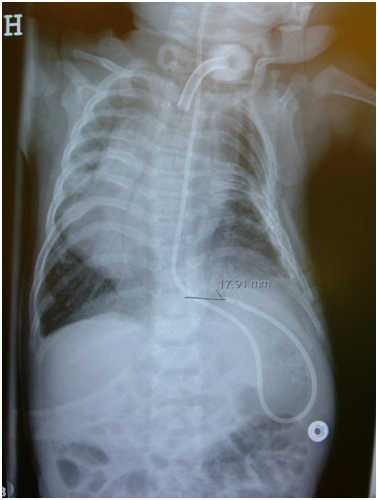

Pre-operative medical history

The patient was born with severe omphalocele and short ribs, but in contrast to Jeune syndrome, the patient also had fused ribs on the left side between ribs 3 and 6. The patient showed immediate signs of respiratory distress following birth and required intubation shortly after birth (Apgar 7/10). Within the first weeks, he underwent several surgeries before his omphalocele was successfully treated. During this period, he was intermittently treated with a respirator, but at the age of four months, he was respirator-dependent and underwent a tracheostomy (Figure 1). At the age of 13 months, he was referred to the spinal unit. X-ray examination revealed both short ribs and fused ribs in the left hemi-thorax (Figure 2a). At 15 and 18 months, he underwent staged opening wedges (thoracic expansion procedures) with VEPTR instrumentation bilaterally (Figure 2b). Initially, after these procedures, his respiratory function was greatly improved; at the age 28 months, he was finally weaned off the respirator, and his tracheostomy was closed. The patient underwent standard lengthening procedures every 6 months. At the age of 6 years (2009), his respiratory parameters included a forced vital capacity (FVC) of 25% and a forced expiratory volume (FEV) of 25%; later that same year, he was diagnosed with pulmonary hypertension (90 mmHg systolic, normal range 15-30 mmHg). He was treated with sildenafil to reduce his pulmonary hypertension in 2010 (7 years old), but at this stage, his respiratory status started to worsen. Initiation of bi-level positive airway pressure treatment increased the patient’s wellbeing. In May and October of 2010, the left side and posterior thoracic rib cage were revised, respectively, with osteotomy of the posterior chest wall like the primary surgeries in 2004. At this time, the posterior and lateral chest walls were fully fused. At the age of 8 years, his respiratory status was rapidly deteriorating, and posterior revision surgery with resection of the posterior wall had no further positive influence on his respiratory function. The patient’s physical condition worsened, and his respiratory status was even more characteristic of severe TIS. By this time, he could perform only short walks with increased strain, and the surgeons, parents and the patient did not foresee a benefit of further VEPTR surgery.